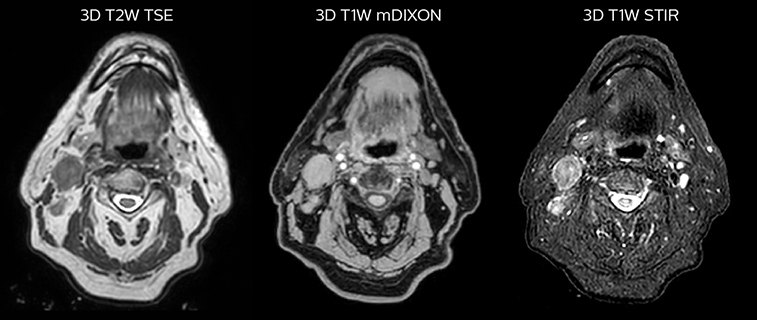

T2W 3D, 3D STIR and mDIXON MRI scans.

Comparison of CT simulation scan (left) and T2W 3D MRI (right)